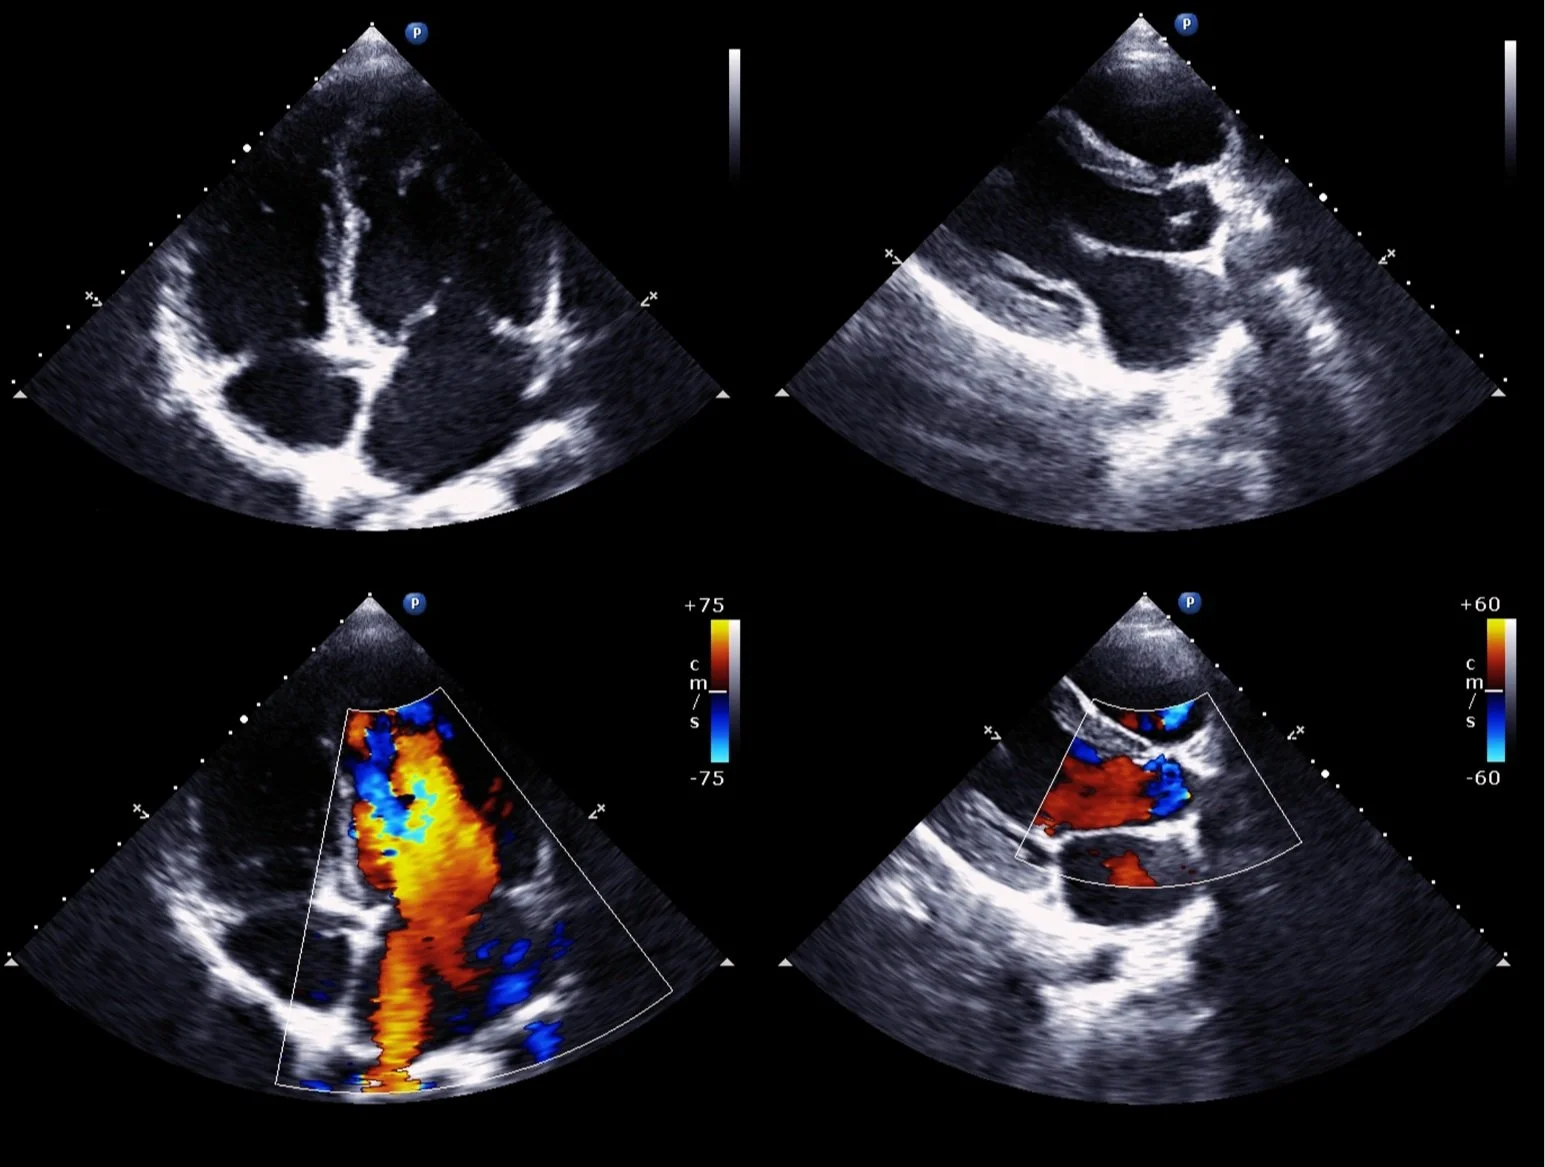

We utilize the latest diagnostic tools, including echocardiograms, stress tests, and vascular imaging, to ensure early detection and effective treatment of heart disease.